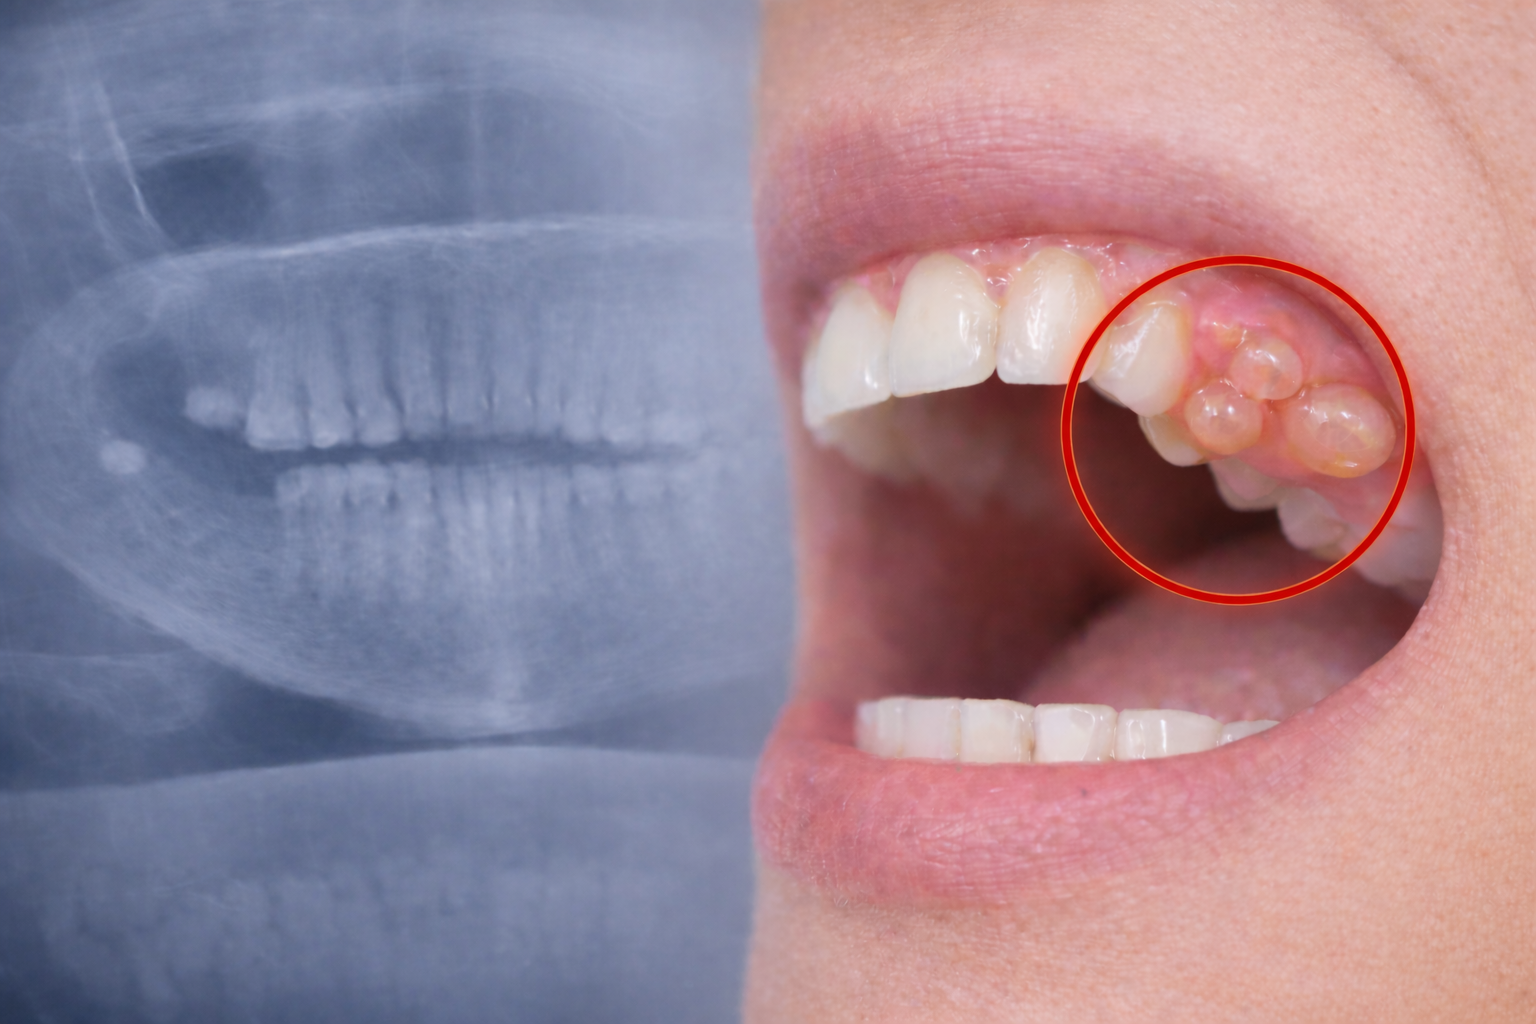

Benjolan di Gusi Tidak Sakit? Waspada Kista Gigi yang Bisa Merusak Tulang Rahang

Kista gigi adalah kantung berisi cairan atau jaringan patologis yang terbentuk di sekitar gigi, akar gigi, atau jaringan mulut.

Gejala Kista Gigi yang Sering Diabaikan

• Benjolan di gusi atau dalam mulut

• Tidak sakit (ini yang membuat banyak orang terlambat sadar)

• Kadang terasa penuh atau menekan

• Nyeri jika sudah terinfeksi

• Gigi terasa goyang tanpa sebab jelas

Sebagian besar kasus ditemukan secara tidak sengaja saat rontgen.

Kista gigi bukan kasus langka.

Studi di Indonesia menunjukkan hingga 10–18% pasien yang diperiksa ternyata memiliki kista dan banyak di antaranya tidak menyadarinya karena tidak menimbulkan rasa sakit.